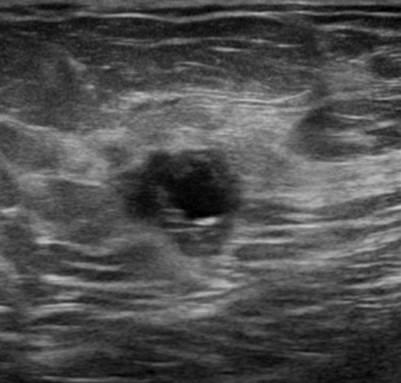

Ung thư vú - Ảnh 3

Ung thư vú

» Thông tin: Nữ giới – 50 tuổi.

» Lâm sàng: Kiểm tra sức khỏe.